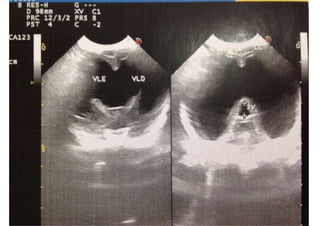

! Diagnostico por imagem

! Ultrassonografia

Convulsões e Epilepsia

ECG-Eletroencefalograma